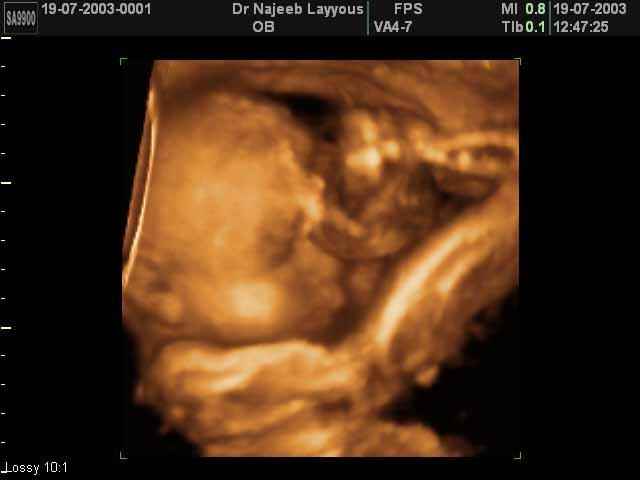

صور جانبية لرأس الجنين بجهاز الالتراساوند ثلاثي الأبعاد | الدكتور نجيب ليوس